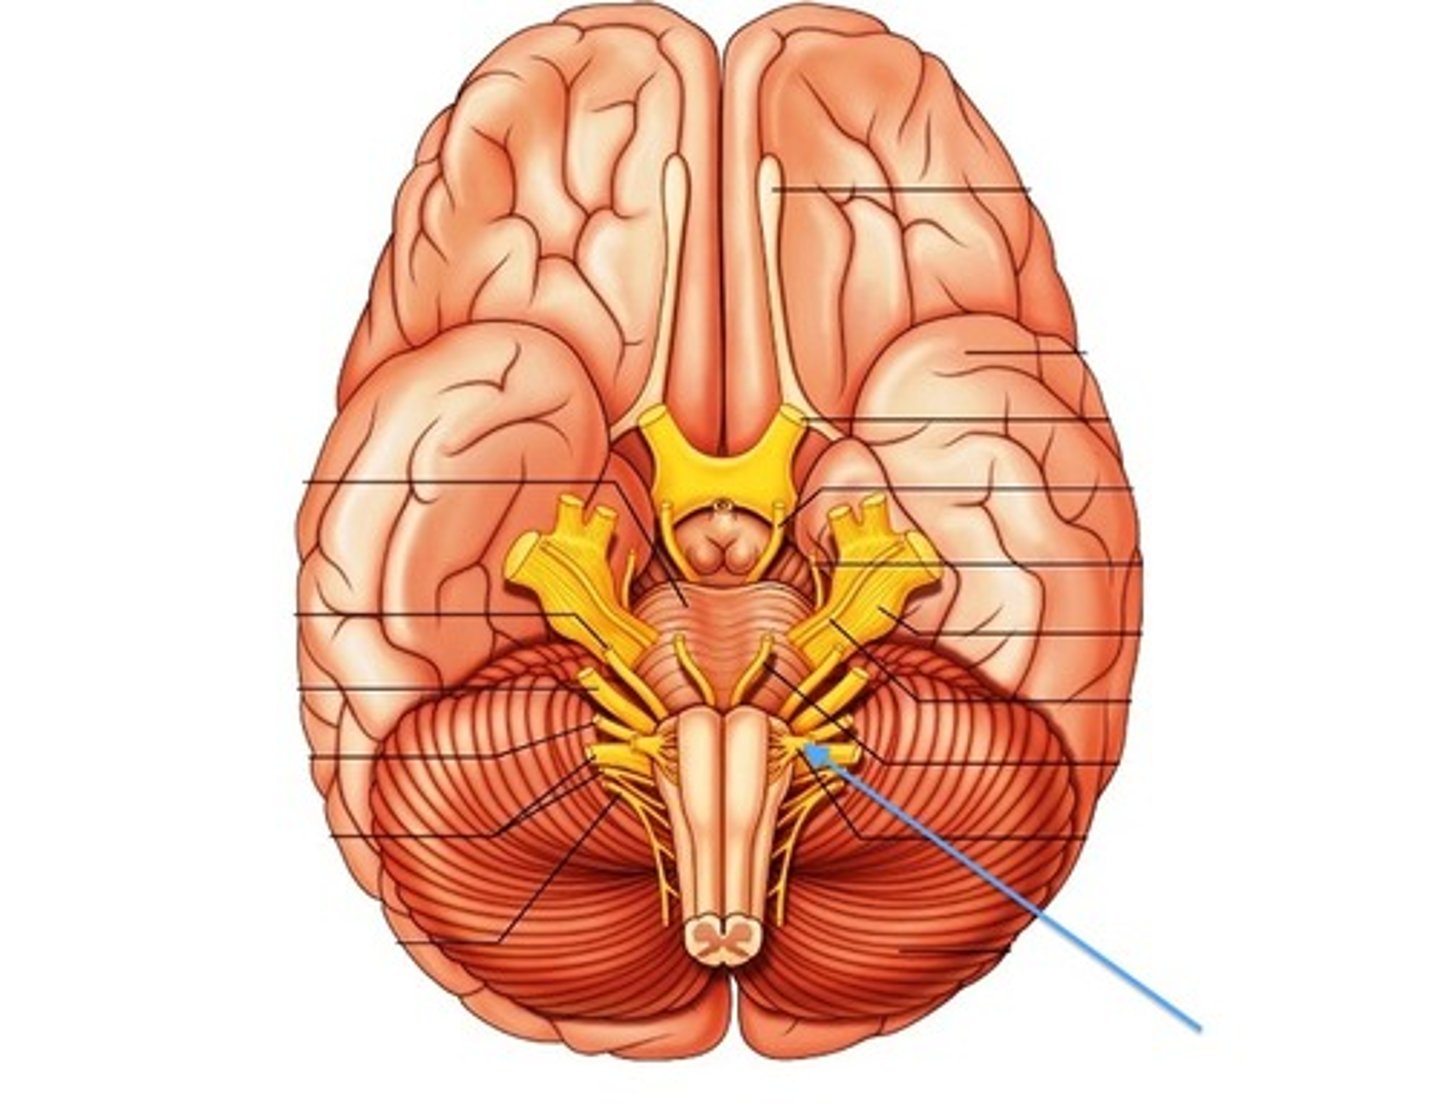

brain stem

continuous with the spinal cord and consists of the medulla oblongata, pons, and midbrain

brain stem

between spinal cord and diencephalon

medulla oblongata

most inferior part of the brain stem; regulates breathing, heart rate, & blood pressure

pons

center structure of the brain stem, located between the midbrain and the medulla oblongata

midbrain

or mesencephalon extends from pons to diencephalon. the pons is the center structure of the brain stem, located between the midbrain and the medulla oblongata